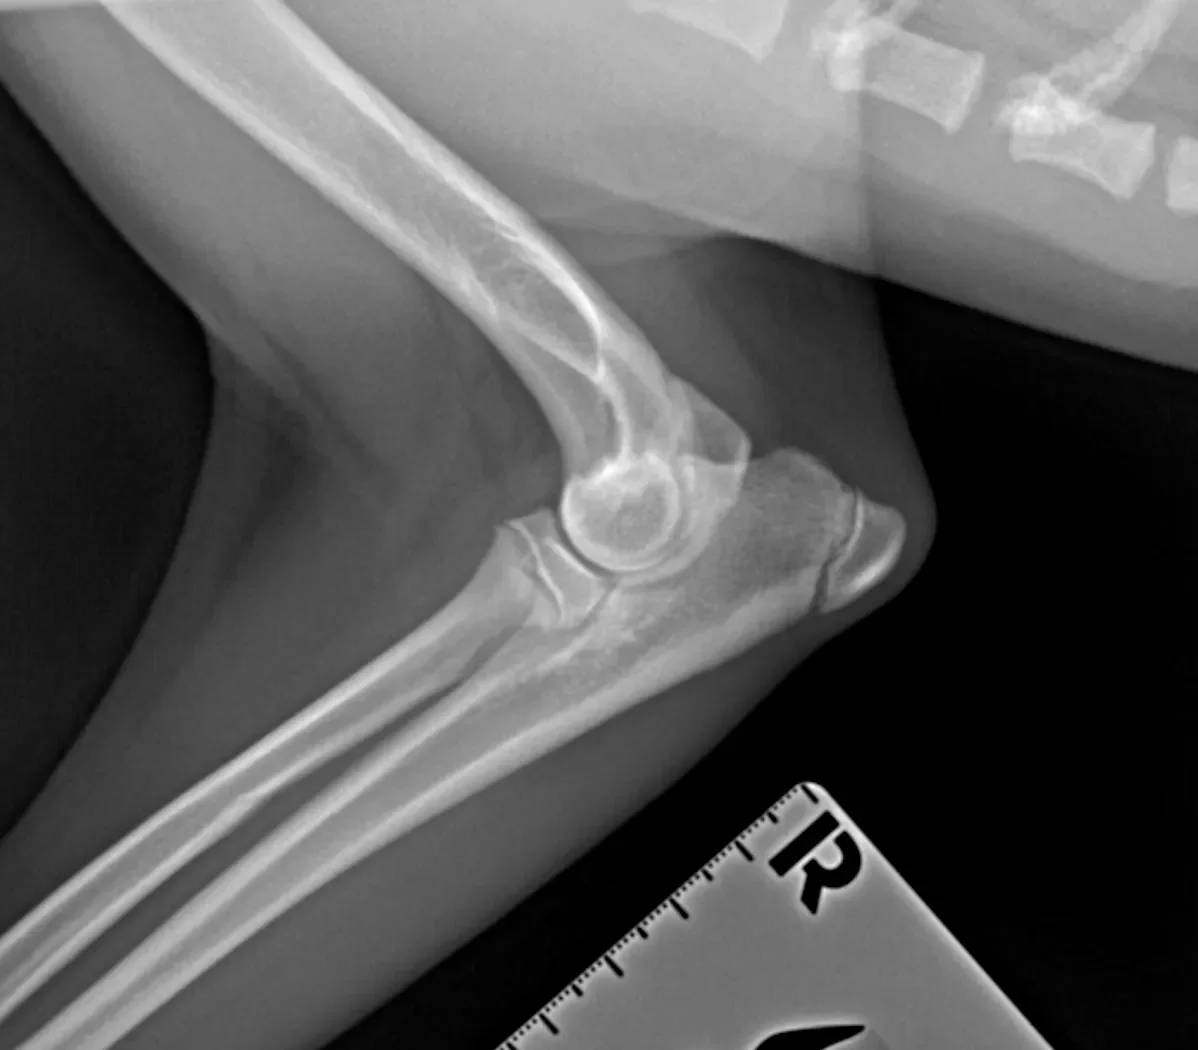

Elbow Clinic

We offer a variety of surgical and medical options for the treatment and management of elbow dysplasia.

We have joined forces with the fantastic team of Specialist and Advanced Practitioner surgeons and nurses from ProVetSurg to provide a unique and holistic approach to the treatment of elbow dysplasia and other orthopaedic and soft tissue conditions.